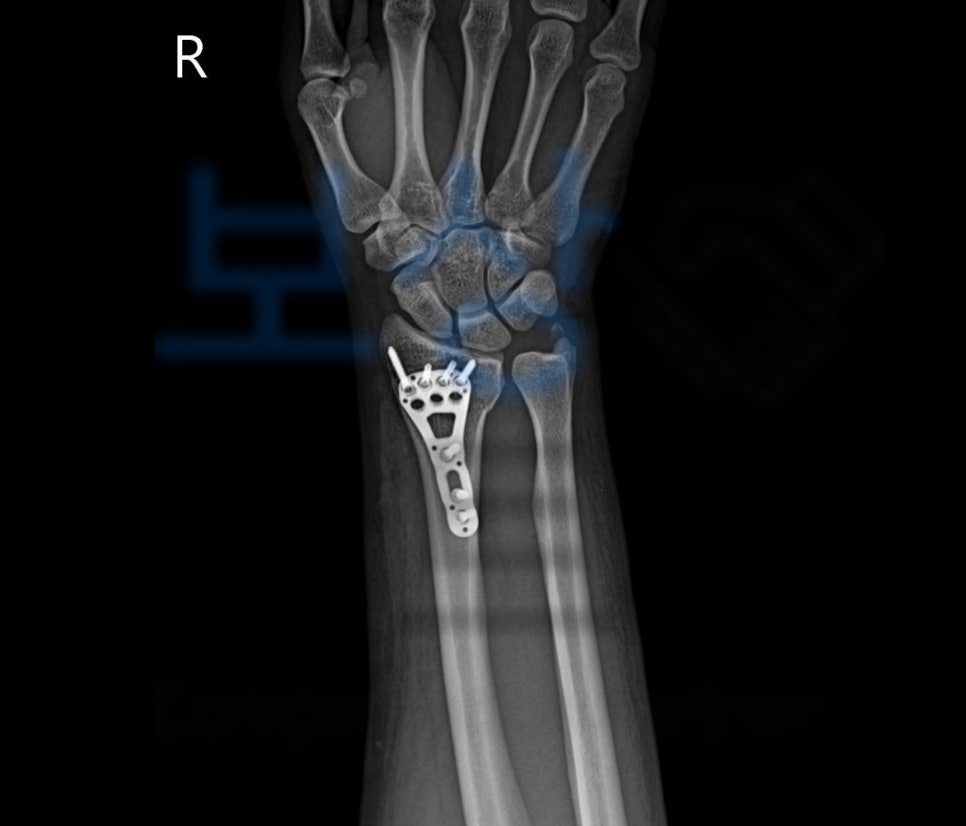

이 사고로 손@@님은 응급실에 내원하셨고

요골 하단의 골절, 즉 손목 골절을 진단받아 금속 고정 후 석고기브스 치료를 받게 되었습니다. 먼저 합의금은 구성 요소는